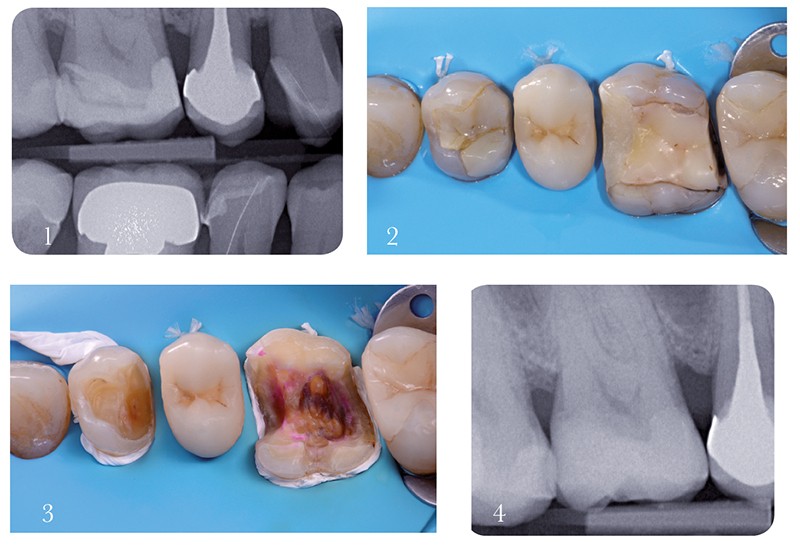

Cas 2 – digue, matrice et caries sous-gingivales proximales

5. Chez ce patient de 91 ans sous traitement médical lourd, les caries en 45d et 46m doivent être traitées avant une hospitalisation d’une durée indéterminée, tout en privilégiant les techniques les plus simples et les moins coûteuses. Un traitement en une séance et des restaurations directes sont choisis.

6. La stratégie initiale est identique à celle mise en œuvre pour le cas 1 : digue, doubles ligatures et téflon permettent de nettoyer les tissus cariés en toute sécurité.

7. Mais quel système de matrice choisir ? Il paraît assez clair qu’un profil proximal convexe et une zone de contact ferme ne peuvent être obtenus qu’au moyen de matrices sectorielles. Mais ces systèmes sectoriels sont plus délicats à utiliser que les matrices circulaires. À l’aide d’une spatule de bouche, un espace est alors aménagé entre le téflon…